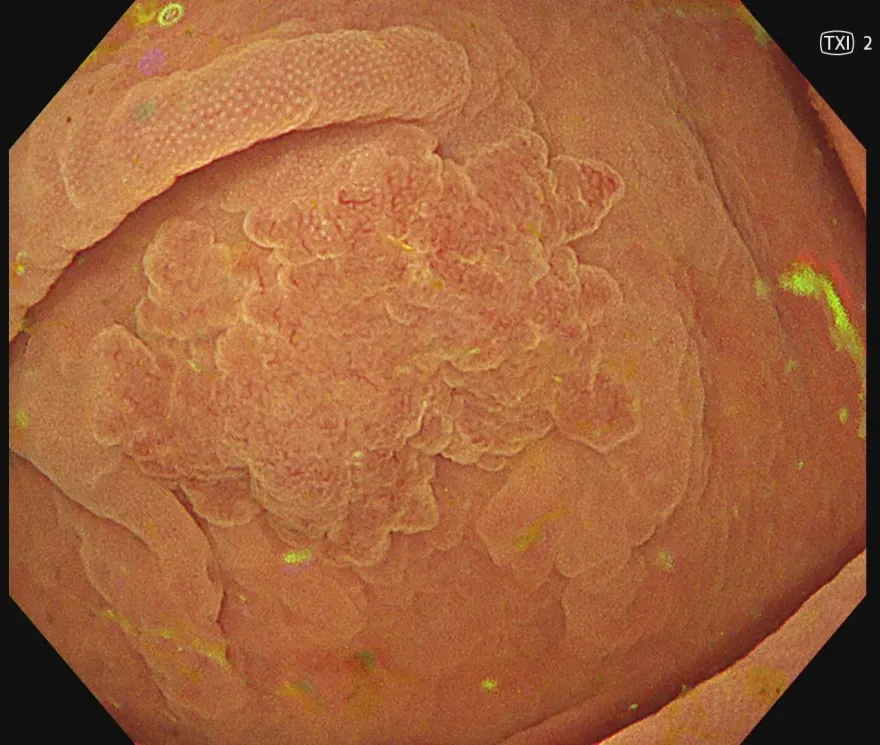

巨型息肉

息肉

腺瘤息肉

腺瘤癌變

腺瘤性息肉

腺瘤型息肉